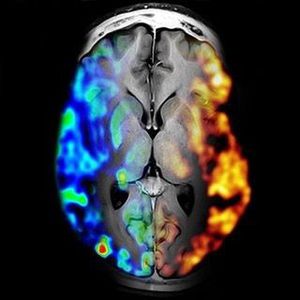

Positron emission tomography/magnetic resonance imaging (PET/MRI) leverages the high soft-tissue contrast and the functional techniques of MR with the molecular information of PET in one single, hybrid imaging technology. This technology, which was recently introduced into the clinical arena in a few medical centers worldwide, provides information about tumor biology and microenvironment. Studies on indirect PET/MRI (use of positron emission tomography/computed tomography (PET/CT) images software fused with MRI images) have already generated interesting preliminary data to pave the ground for potential applications of PET/MRI. These initial data convey that PET/MRI is promising in neuro-oncology and head & neck cancer applications as well as neoplasms in the abdomen and pelvis. The pediatric and young adult oncology population requiring frequent follow-up studies as well as pregnant woman might benefit from PET/MRI due to its lower ionizing radiation dose. The indication and planning of therapeutic interventions and specifically radiation therapy in individual patients could be and to a certain extent are already facilitated by performing PET/MRI.